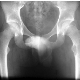

merhabalar.Bugün mr sonuçlarımı aldım.Sonucu şu: Lomber lordoz düzleşmiştir.L5-S1 diskinde dejeneratif sinyal kaynı vardır.Lomber vertebra korpus yükseklikleri ve dizilimleri normaldir.Konus medullaris normal lokalizasyondadır.l2-l3, l3-l4 düzeylerinden geçen kesitlerde disklerde herniasyon bulgusu gözlenmemiştir.epidural alan ve nöral foramenler açıktır.l4-l5 diskinde diffüz bulging vardır.Nöral foramenler açıktır.Sinir kökleri serbesttir.l5-s1 diskinde diffüz bulging zemininde posterosnatral-sol subforaminal sol subforaminal düzeye migre herniasyon vardır.Solda s1 sinir köküne belirgin bası izlendi.sağ nöral foramen açıktır.sinir kökü serbesttir. yorumlarsanız çok mutlu olurum.Şimdiden teşekkür ederim.

Ameliyat olmanızı gerektirecek tarzda bel fıtığınız var.